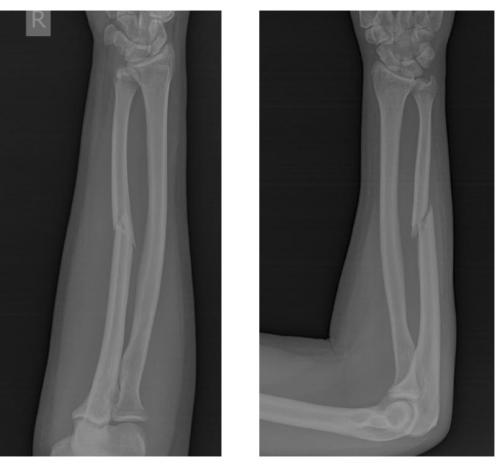

Клинический пример хирургического лечения перелома локтевой кости.

Пациент П. 39 лет, получил перелом локтевой кости в результате прямой травмы (падение на бордюрный камень с упором на согнутую в локтевом суставе руку).

Обратился в РТП, была наложена гипсовая повязка, лечился консервативно.